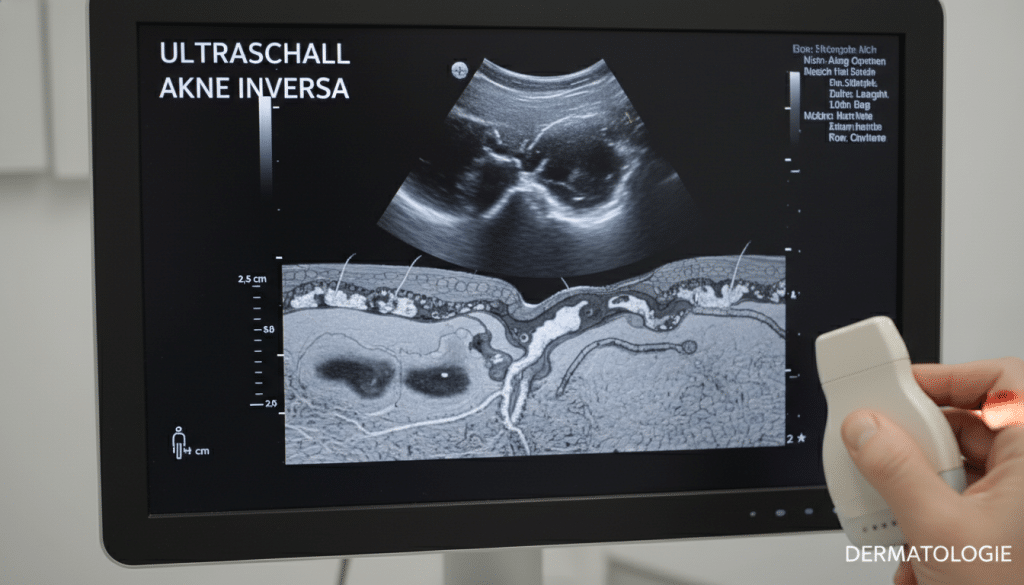

Der Ultraschall Akne inversa zeigt, was an der Oberfläche nicht zu sehen ist. Damit lassen sich tiefe Abszesse, Entzündungsherde im Unterhautfettgewebe und mögliche Fistelgänge darstellen. Das hilft, schmerzhafte Bereiche zu erklären und die weitere Planung zu strukturieren.

| Ultraschall Akne inversa | Darstellung tiefer Abszesse, subkutaner Ausdehnung und möglicher Fistelgänge; Unterstützung bei der Planung weiterer Schritte | Wie weit reicht die Entzündung unter der Haut, und gibt es versteckte Hohlräume? |